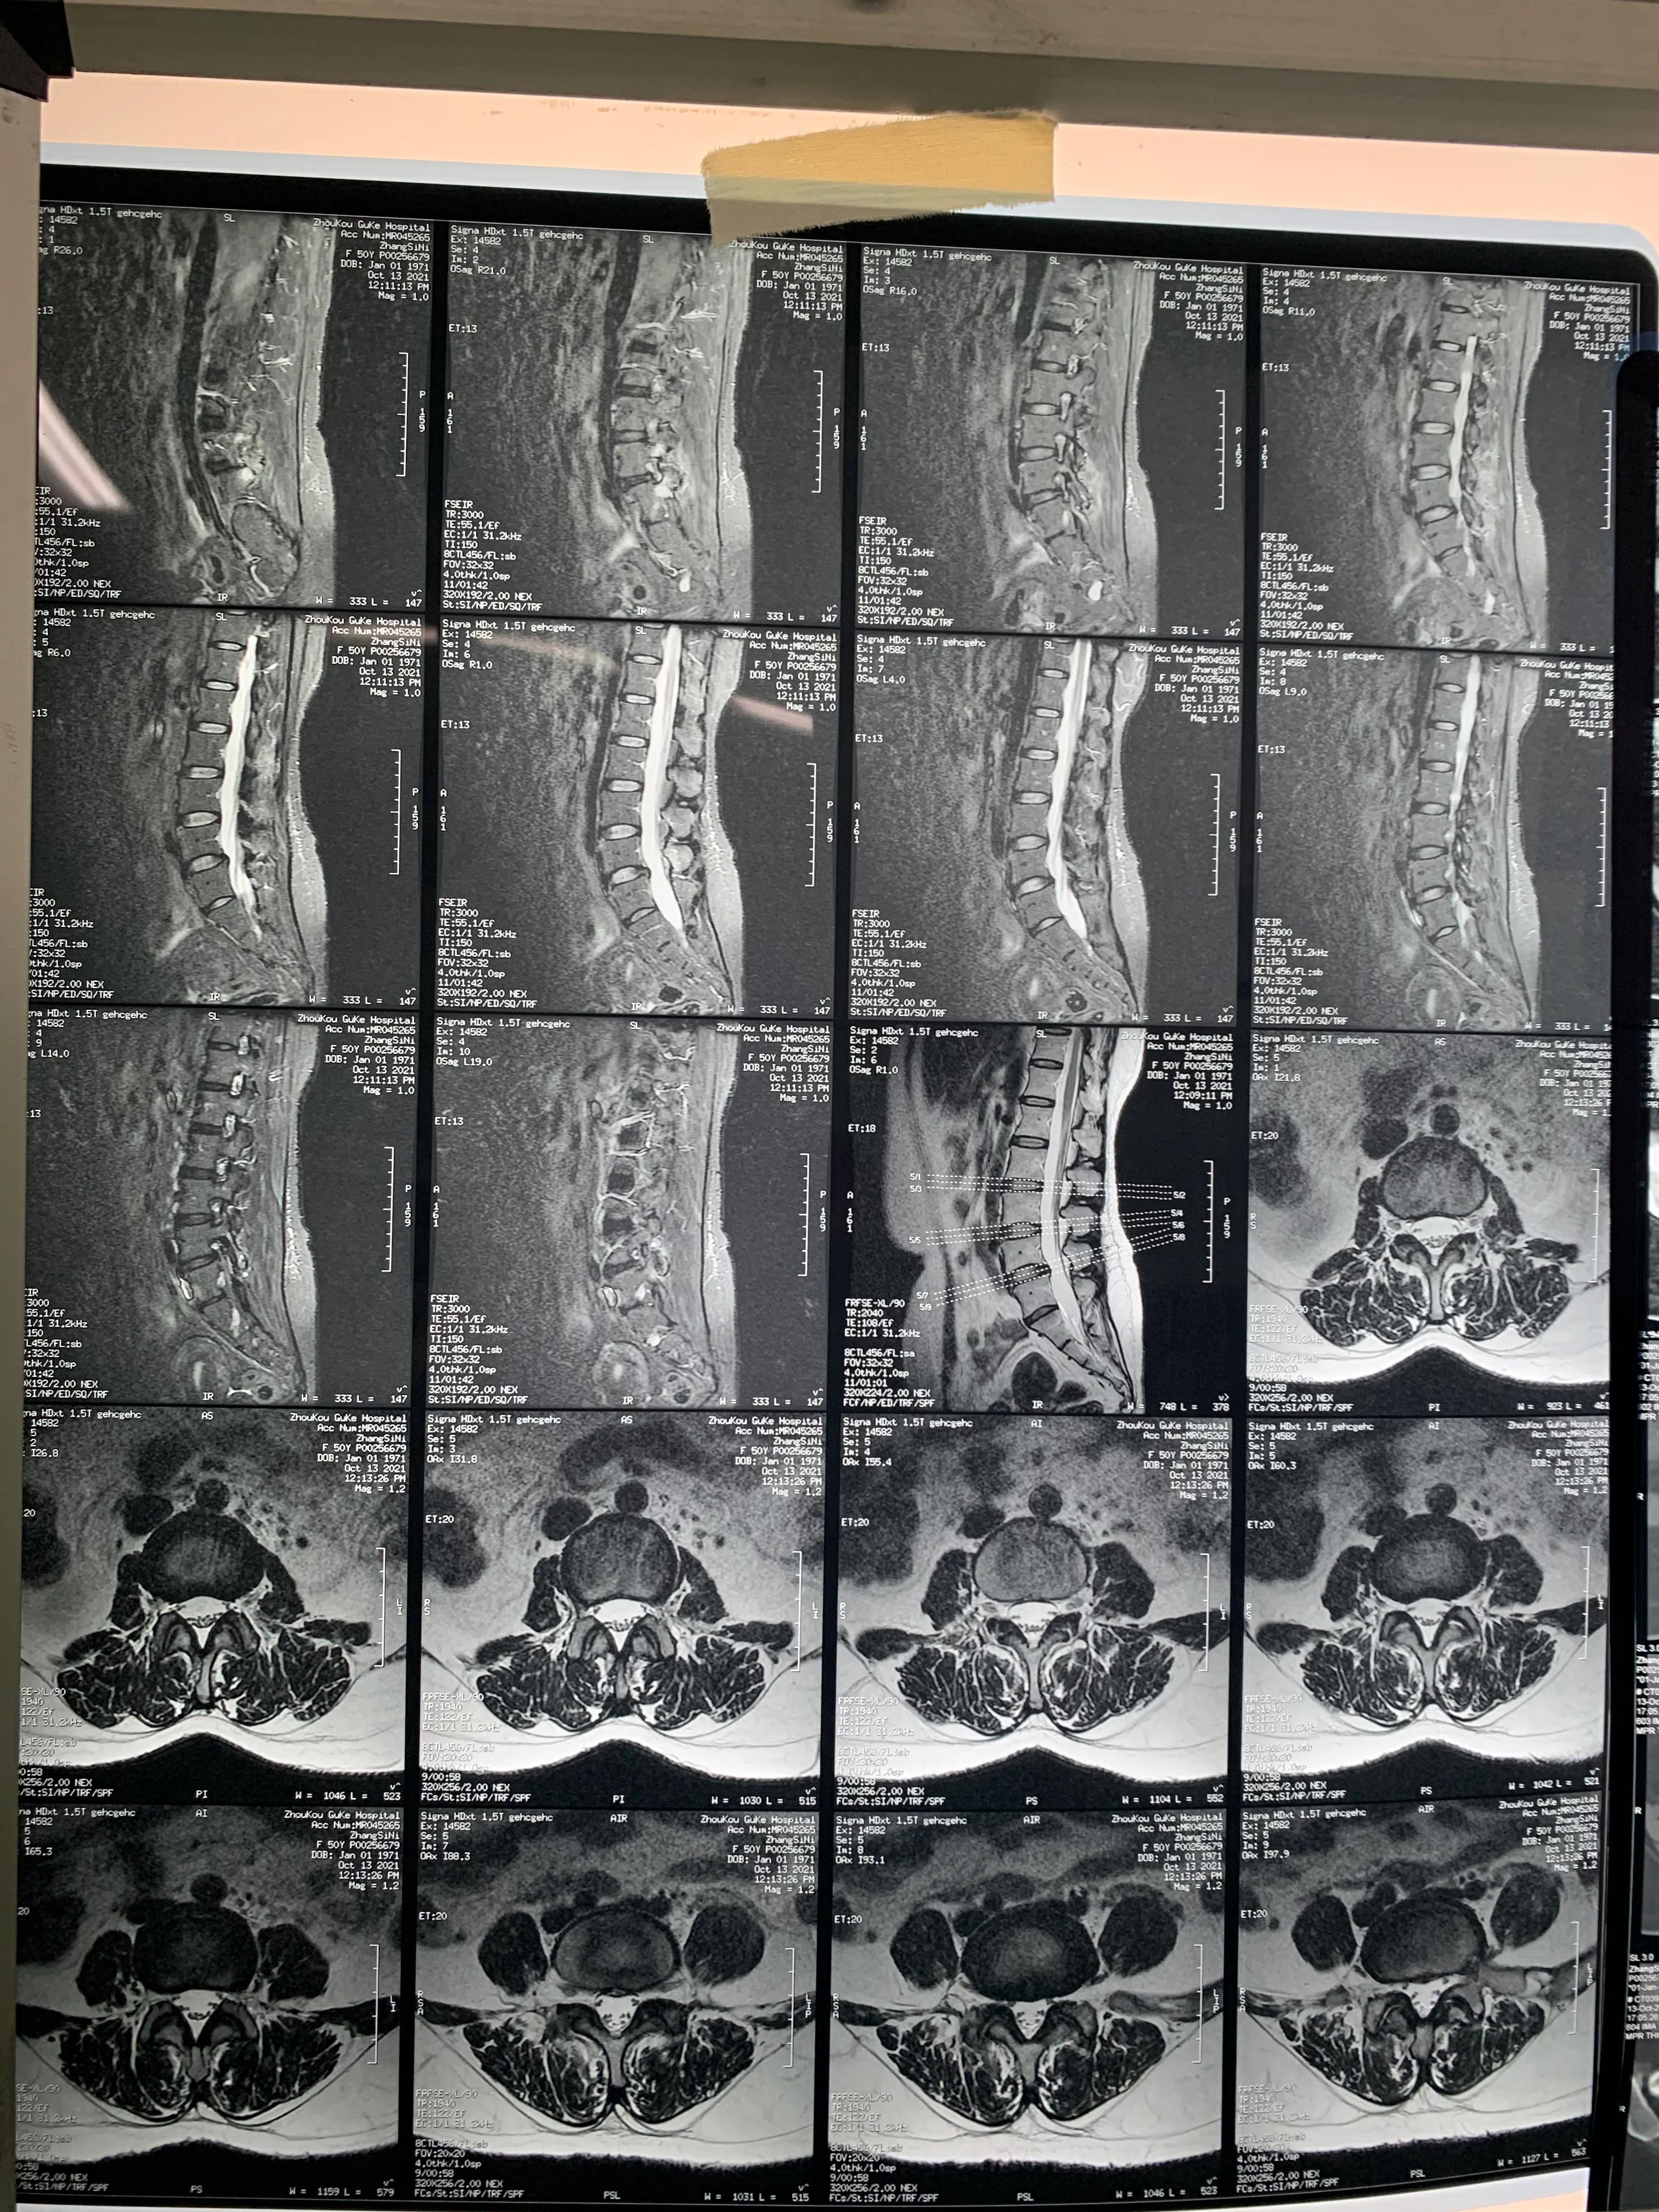

核磁